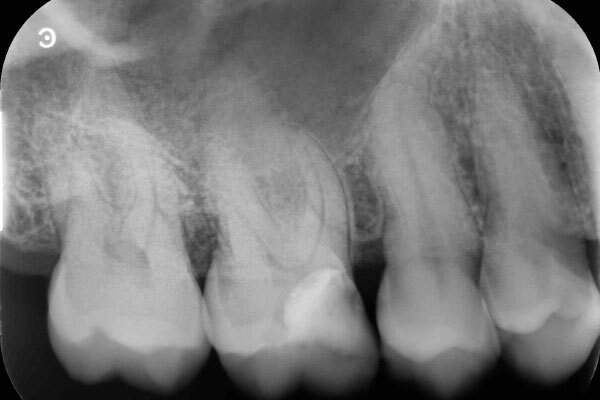

3か月後のデンタルX線写真です。

神経も正常に生きており、レントゲン写真からも異常所見は認めません。

今回の症例は虫歯の範囲が大きかったので、型どりを行い、部分的に被せる治療を行いました。

終了後も症状はなく問題なく使用できているとのことです。周りの歯の虫歯に関しては近くの歯科医院で進めるとのことでした。